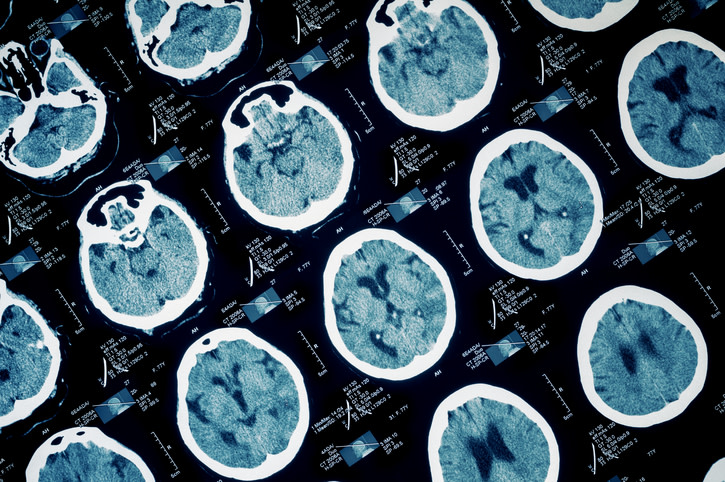

La epilepsia es una enfermedad cerebral crónica, que se caracteriza por cambios en el tejido que vuelven al cerebro (o parte de este) demasiado excitable o irritable, lo que deviene en diferentes episodios de convulsiones (movimientos involuntarios que afectan una parte del cuerpo o su totalidad). Estos pueden variar en frecuencia e intensidad.

Se suelen clasificar las convulsiones en dos grandes grupos: focales o generalizadas. Las primeras, también llamadas parciales, ocurren cuando los episodios se producen por la actividad en una sola parte del cerebro. Durante estas se puede o no, perder el conocimiento. El otro tipo son las generalizadas, que se producen por actividad en todo el cerebro y pueden dividirse en 6 subtipos.

A pesar de los años de investigación, en aproximadamente la mitad de los casos no se puede identificar la causa de la epilepsia. En la otra mitad puede atribuirse a trastornos de desarrollo o lesiones prenatales, enfermedades cerebrales o infecciosas, traumatismo de cráneo o influencia genética. Otros factores de riesgo para desarrollarla incluyen a los accidentes cerebrovasculares o la demencia.

Si los episodios convulsivos continúan con normalidad, lo que se conoce como "epilepsia resistente al tratamiento", el médico puede evaluar la posibilidad de realizar una cirugía. Esta puede consistir en extirpar las células cerebrales anormales que causan la convulsión o en colocar un estimulador del nervio vago, una especie de marcapasos que ayuda a reducir los episodios epilépticos.